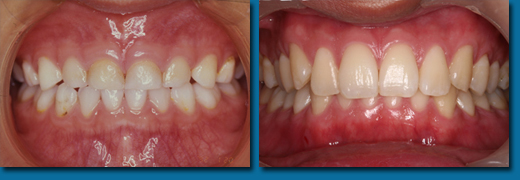

歯並びが悪くなってから治療することを歯列矯正といいますが、乳歯の頃から出てくる歯並びが悪くなる兆候を早期に発見しそれを改善しながらきれいな歯並びの永久歯にしていくことを咬合育成といいます。専門的には歯列矯正と咬合育成は別の物と区別されています。咬合育成は歯並びの予防と考えられ当医院では積極的に取り組み、多くの歯並びの良い子供が育っています。写真の左は乳歯の時、右が永久歯になった時のものです。

咬合育成でおこなうひとつの治療に顎を拡げて永久歯の入るスペースを作るというものがあります。

歯並びの悪い人の多くは顎が小さくて永久歯が並びきらないことが原因になっています。

成長が終わってから矯正治療を受けた方のほとんどが永久歯を4本抜歯してスペースを作って歯並びをきれいにしますが高齢になって歯を失いはじめると最初から歯が4本少ないことは咀嚼をする上でかなりのハンディキャップになります。

なるべく歯を抜かないできれいな歯並びにするには成長期に骨を刺激し、顎を拡げることです。

乳歯から永久歯への生え替わりは6歳くらいから上下の前歯4本から始まり、そして10歳ころから犬歯、奥歯と生え替わり12歳ころで終わります。

はじめに前歯の4本がきれいに並ばなければその後の犬歯、奥歯の生え替わりで歯並びはどんどん悪くなってしまいます。

そのため上下の前歯4本が生え替わる時期に顎を拡げ、きれいに並べておく必要があります。

あまり知られていませんが永久歯の奥歯は乳歯よりも小さいので前歯4本がきれいに並んでいれば奥歯はほとんどがきれいに並びます。

乳歯の時からスペース不足の傾向はでているので個人差はありますが5歳くらいからなるべく早く開始すると安心です。

遅くても8歳になる前には始めなければこの治療法は選択できません。